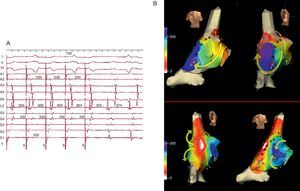

Figura 4. Cartografía electroanatómica (Navx®) de taquicardia auricular focal originada en la aurícula izquierda paraseptal. La imagen del torso indica la posición de las vistas (anterior a la izquierda, posterior con angulación caudal a la derecha). La escala de tiempo, a la izquierda, marca blanco el inicio de activación y violeta el final. Obsérvese la propagación centrífuga uniforme (blanco → amarillo → verde → azul → violeta) que converge en la aurícula izquierda posterior.

Figura 12. A: cartografía electroanatómica (Navx®) en visión anterior, de un circuito de taquicardia auricular macrorreentrante en torno al anillo mitral en paciente sin antecedentes quirúrgicos; obsérvese la amplia zona inexcitable de bajo voltaje (en gris) en la aurícula izquierda posterosuperior. B: cartografía en visión oblicua anterior derecha de una taquicardia auricular focal muy lenta (ciclo, 430 ms) inducible tras la interrupción de la taquicardia auricular macrorreentrante con aplicaciones de radiofrecuencia entre la zona de bajo voltaje y el anillo mitral (puntos rojos); esta taquicardia auricular focal se origina en la vena pulmonar superior derecha (área blanca); como en el caso de la figura 6, una línea de bloqueo obliga al giro del frente de activación que termina al otro lado de esta zona de bloqueo (azul-violeta). BV: bajo voltaje; LC: longitud del ciclo.

Figura 13. Cartografía electroanatómica (Navx®) en visión anterior (A) y posterolateral derecha (B) de una taquicardia auricular macrorreentrante girando en torno a la vena pulmonar superior derecha. Obsévense las zonas inexcitables de bajo voltaje, especialmente en la aurícula izquierda posterior.